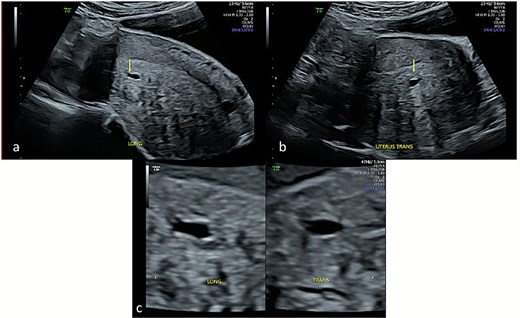

Transabdominal ultrasound of the uterus demonstrating cystic sub-endometrial spaces that were mistaken for a gestational sac in earlier ultrasound scans. The sub-endometrial space is demonstrated in longitudinal (a) and transverse planes (b) and under magnification (c) with a notable absence of decidual reaction around the cystic space.

Repeat specialist ultrasound (Fig. 1) identified a right interstitial ectopic pregnancy measuring 27 × 24 × 26 mm, with a decidual reaction, a foetal pole and absent cardiac activity. The gestational sac did not communicate with the endometrial cavity. Diffuse cystic adenomyosis was noted (Fig. 2). Retrospective review indicated that sub-endometrial microcysts had been mistaken for a gestational sac on earlier scans (Fig. 3).